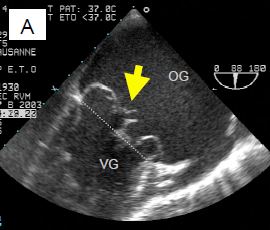

L'échocardiographie démontre que la maladie dégénérative peut prendre plusieurs aspects (Figure 11.64).

Figure 11.64 : Images ETO d’insuffisance mitrale sur dégénérescence myxoïde. A : excès de tissu avec ballonnisation, épaissisement localisé et prolapsus des deux feuillets ; la flèche indique le déplacement de l’extrémité des feuillets en arrière du plan de l’anneau mitral (trait pointillé). B : prolapsus isolé de P2. C : prolapsus de P2 avec rupture de cordage (indiqué par la flèche). D : rupture complète de muscle papillaire avec fragment de pilier attaché à l’extrémité du feuillet antérieur.